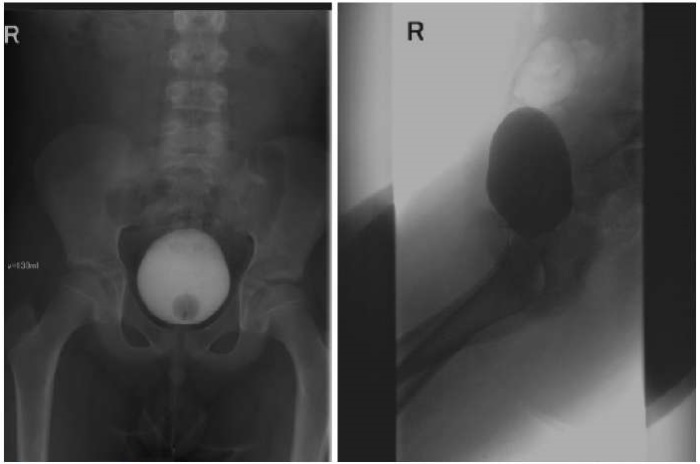

Мальчик, 1 год 2 месяца, с рождения наблюдался с объемным образованием в перианальной области. В возрасте 10 месяцев госпитализирован с клиникой острого парапроктита, проведено вскрытие и дренирование абсцесса, стандартный курс антибактериальной терапии. После стихания острых симптомов воспаления последовательно выполнены УЗИ и фистулография. Результаты исследований выявили, что полость абсцесса имеет значительную протяженность в мягких тканях и сообщается с мочевым пузырем, сделано предположение о наличии врожденного пузырно-промежностного свища. Ребенок выписан с рекомендациями повторного обследования через месяц, но спустя несколько дней госпитализирован повторно с жалобами на беспокойство при микции и неприятный запах мочи; продолжена антибактериальная терапия до полного купирования воспалительных явлений и нормализации лабораторных показателей.

Спустя два месяца появился отек, покраснение и болезненность в области мошонки справа. Госпитализация в отделение детской хирургии ММКЦ «Коммунарка». При осмотре в перианальной области на девяти часах условного циферблата визуализировано свищевое отверстие диаметром 0,1–0,2 см без отделяемого (рис. 12). С учетом предыдущего анамнеза принято решение о проведении цистографии, в результате которой при микции обнаружен затек контраста вне мочевого пузыря в свищевой ход. Выполнена цистоскопия — свищевое отверстие не визуализировано. На серии снимков МРТ малого таза в промежностной клетчатке справа обнаружен свищевой ход протяженностью 35 мм, шириной 13 мм. Накопленный нами ранее опыт позволил предположить наличие удвоения уретры. Принято решение об оперативном лечении: в перианальной области выполнен разрез, тупым и острым путем выполнена мобилизация свища (рис. 13), который интимно прилегал к m. levator ani и стенке прямой кишки до условного вхождения последнего в шейку мочевого пузыря, лигирован, пересечен. Сообщения свищевого хода с прямой кишкой не выявлено. При гистологическом исследовании установлено, что стенка свищевого хода представлена фиброзно-мышечной и зрелой жировой тканью с выстилкой из многослойного плоского неороговевающего и переходного эпителия.

Рисунок 12.

Локальный статус. Свищевое отверстие на 9 часах условного циферблата (фото из архива кафедры детской хирургии и урологии — андрологии им. Л.П. Александрова)

Figure 12.

Local status. Fistula opening at 9 o’clock on a conventional clock face (photo from the archive of the L.P. Alexandrov Department of Pediatric Surgery and Urology-Andrology)